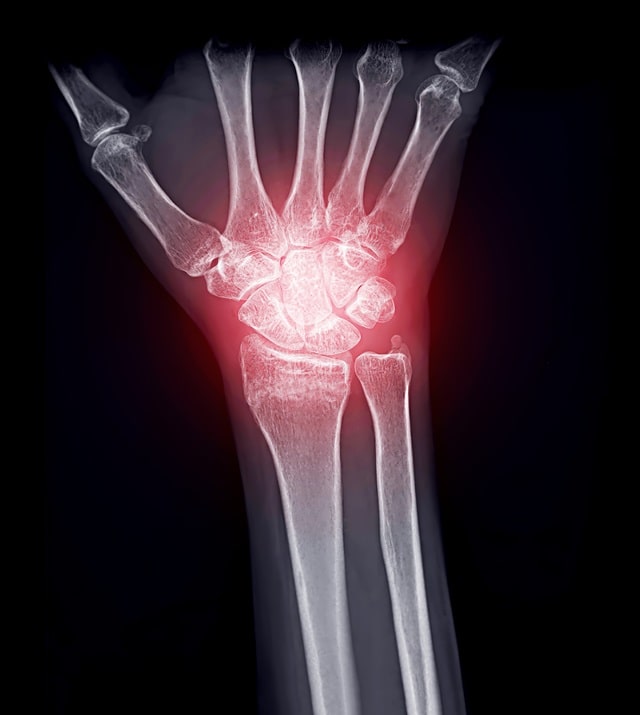

류마티스 관절염은 관절에 염증이 생기는 자가면역질환입니다.

자가면역질환은 몸의 면역체계가 실수로 스스로 조직을 공격해 염증과 조직 손상을 일으키는데 류마티스 관절염의 경우 관절의 안쪽 구조인 활액에 염증이 생겨 통증과 부기, 경직이 발생합니다.

주로 연골에 영향을 주는 손 골관절염과 달리 류마티스 관절염은 연골, 뼈, 인대 등 관절 내 여러 구조물에 손상을 줄 수 있습니다.

류마티스관절염은 여러 관절에 동시다발적으로 영향을 주는 경우가 많고 피로감, 발열, 체중 감소 등의 전신 증상을 유발할 수 있습니다.

- 류마티스 관절염: 혈액검사상 염증수치 상승, 류마티스 관련인자 (anti CCP, rheumatoid factor)양성, x-ray 상 관절 미란(침식)